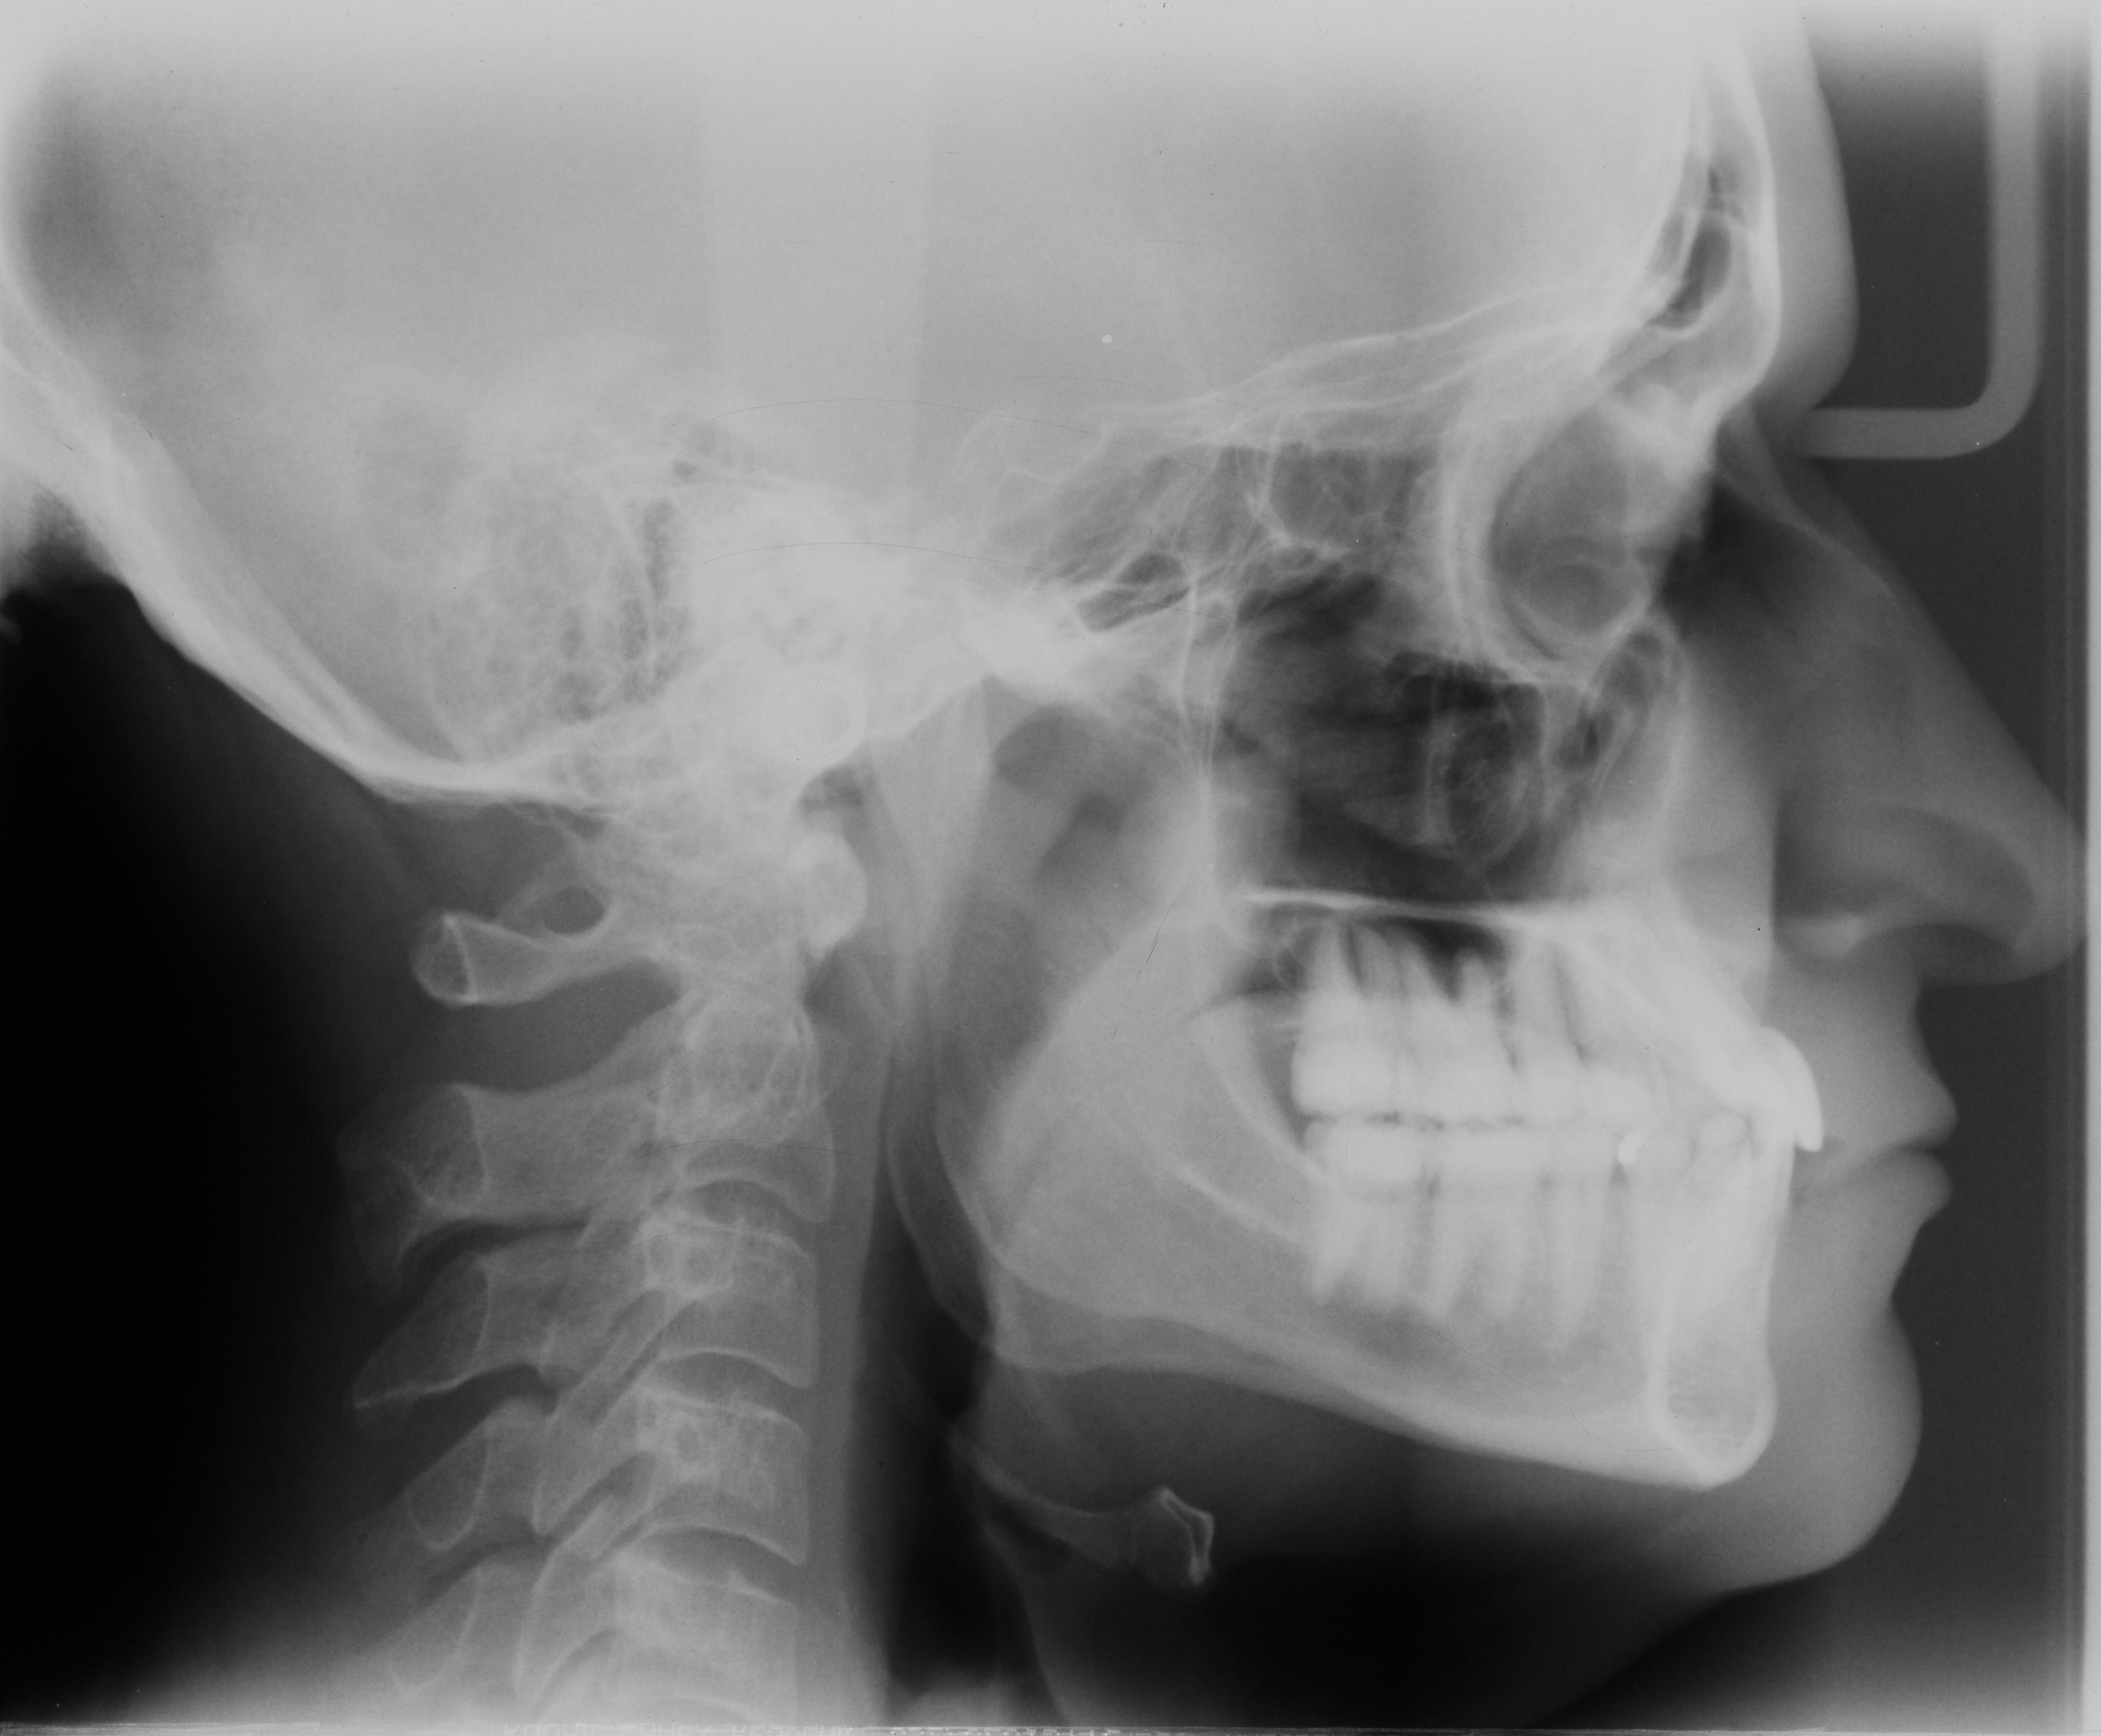

Fig 5. Preoperative cephalometric view highlighting maxillary deficiency, brachycephalic craniofacial phenotype, short upper face height, and maxillary retrognathia. Thin facial bone and proclined incisors are also noted.

Figure 5

Fig 16. Postoperative cephalometric view. Note augmented facial bone in both arches. Buccal root torque/uprighting of the mandibular central incisor has been accomplished for improved inter-incisal angle position and improved iomechanics.

Figure 16